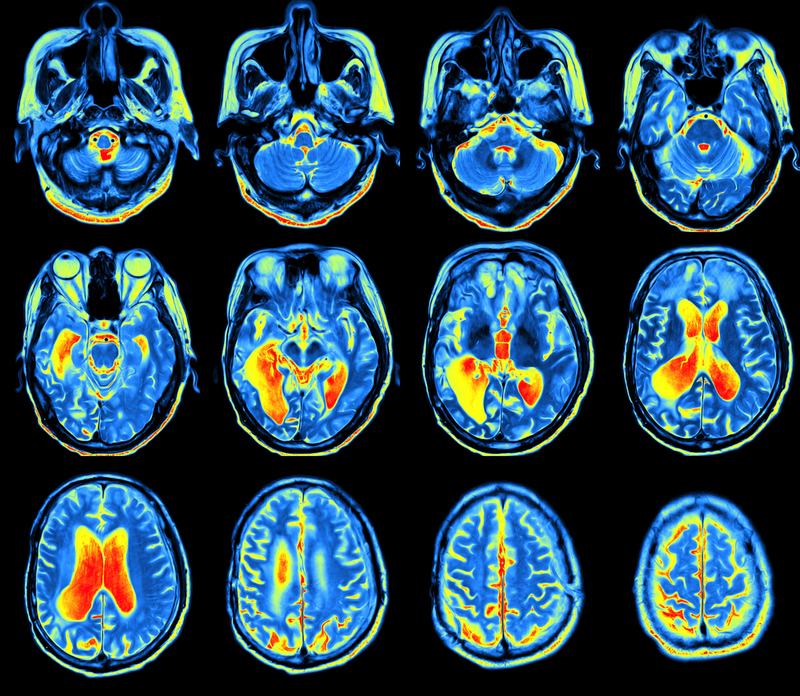

Advanced MRI may hold the key to objectively measure neuroimaging findings or quantitative biomarkers for migraine to better identify the various migraine phenotypes. This may predict which patients may develop more severe phenotypes, and possibly even their responses to treatment, according to a new review published in the Expert Review of Neurotherapeutics.

Overall, observations of gray matter structural abnormalities are mixed and conflicting. Nevertheless, the authors find that gray matter structural parameters observed on MRI could be used to distinguish chronic migraine vs episodic migraines vs no migraine.

Furthermore, structural and functional abnormalities on MRI may be linked to the chronification of episodic migraine, as well as the reversion from chronic to episodic migraine. In one study reviewed by the authors, after prophylactic treatment with onabotulinumtoxinA (BoNT-A) for migraine, responders to treatment demonstrated cortical thickness changes as compared with non-responders.

As for white matter microstructural changes on MRI, the authors comment that current research on the topic is controversial, and it’s unclear whether such white-matter changes cause or are caused by migraine attacks.

Dr. Russo and colleagues suggest that visual cortex responses observed on MRI may serve as “therapeutic biomarkers,” which could gauge the efficacy of preventive treatment and optimize therapeutic effect.

The reviewers point out that, on MRI, the altered functional connectivity (FC) interactions between brainstem brain-modulating circuits and limbic areas could contribute to migraine type and pathology, and be used to model a robust “neurolimbic pain network.” Moreover, FC data from previous resting-state studies have been employed to develop FC brain maps that have been used to distinguish migraneurs from non-migraineurs.

Researchers hope that, someday, manifestations such as visual cortex responses or white matter microstructural changes observed on MRI may become therapeutic biomarkers in the management of migraine.